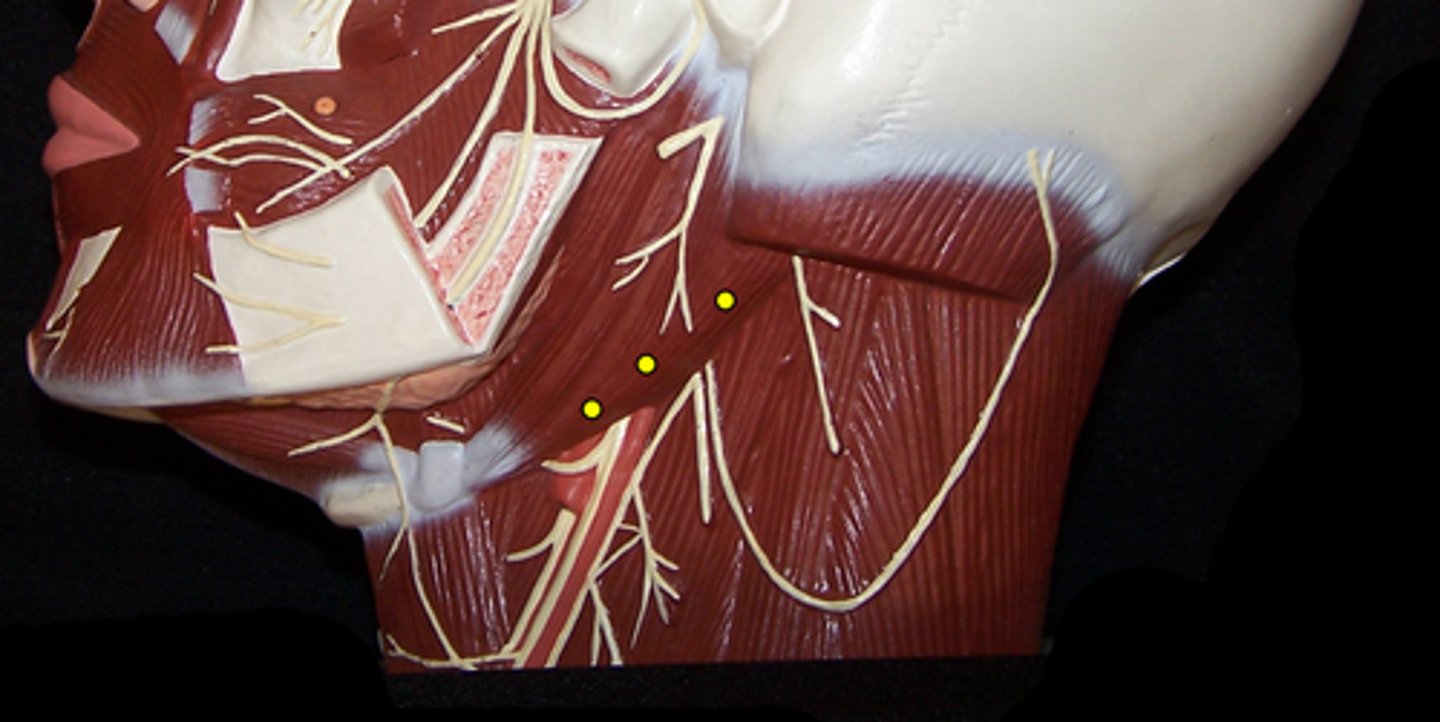

Anterior Belly of the Digastric

Posterior Belly of the DIgastric

Stylohyoid

Mylohyoid

Sternohyoid

Omohyoid

Sternocleidomastoid